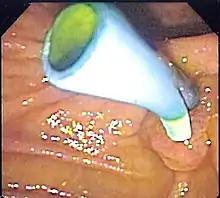

| Pancreatic and biliary stents provide pancreatic and bile drainage from the gallbladder, pancreas, and bile ducts to the duodenum in conditions such as ascending cholangitis due to obstructing gallstones. | ![]() Endoscopic image of a biliary stent seen protruding from the ampulla of Vater at the time of duodenoscopy |